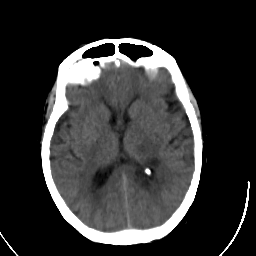

Stroke CT #3 -- Slice #13

[Home][Help][Clinical] Slice 13